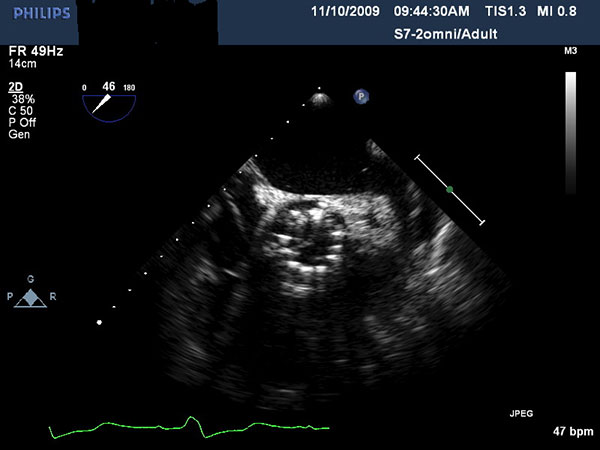

Echocardiography is important to confirm the severity of aortic stenosis, rule out bicuspid aortic valve (which a relative contra-indication) and to size the aortic annulus and left ventricular outflow tract (LVOT) (Figure 1). It is also necessary to assess for concomitant Mitral valve disease. Mild to moderate mitral regurgitation (MR) is frequently associated with AS in elderly patients but does not usually require any surgical intervention and does not represent a contraindication for TAVI. However, severe MR with bulky mitral annular calcification involving the LVOT has been associated with worse midterm outcome and increased risk of para-valvular leak (2).

CT scan of the chest, abdomen and pelvis should be performed with three-dimensional reconstruction preferably with contrast if kidney function allows. The acquisition is performed with cardiac gating during the thoracic phase to assess the location of the coronary ostia in relation to the aortic annulus which is supposed to be > 10 mm to allow safe implantation of the valve (2). Additional assessment of the aorta CT scan and TEE are also important to delineate the morphology and measure the dimensions of the aortic root (Table, Figure 2).